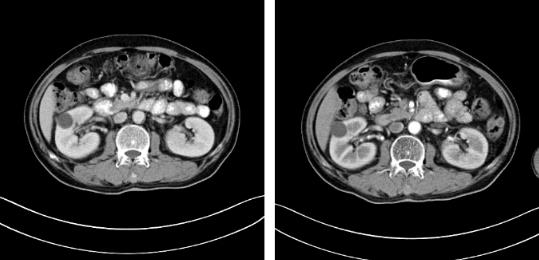

隨著時間的推移,安圖叔叔身體開始發(fā)生明顯變化,腰疼的癥狀得到緩解,血尿的次數(shù)明顯減少,睡眠質(zhì)量有明顯的改善。以前上廁所都是一件很痛苦事情,如今逐漸正常。安圖叔叔的病情得到改善,在一次次的復(fù)查中得到主治醫(yī)生王峰的佐證。過去的兩年里,安圖叔叔一直遵循醫(yī)生的囑咐,按時服藥定時回院復(fù)查,到目前為止是安圖叔叔第9次來院復(fù)查。安圖叔叔的兒子說道:“我每次帶父親來檢查都有新發(fā)現(xiàn),腫瘤在一天天的變小,我們很相信醫(yī)生的話,他們會給我們最好的治療方案,如今已過去兩年,父親身體和精神慢慢轉(zhuǎn)好,這是我們所希望的。”

自2017年做冷凍消融術(shù)后,安圖叔叔兩年多時間腫瘤不僅沒有增長并多次檢查沒有復(fù)發(fā)跡象。安圖叔叔認為,冷凍給他帶來新的希望,又一次看到復(fù)大創(chuàng)造新的奇跡。